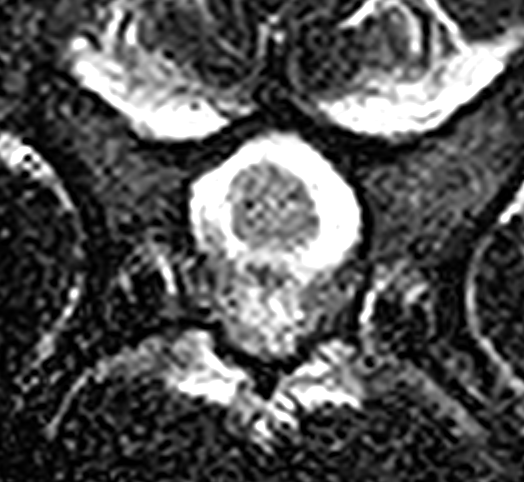

MRI画像検査です。頚椎2−3の圧迫が確認されました。

頚椎3−4での圧迫が確認されました。

椎体中央部の正常な脊髄です。脊髄周囲には脳脊髄液があり、狭窄がないのがわかります。